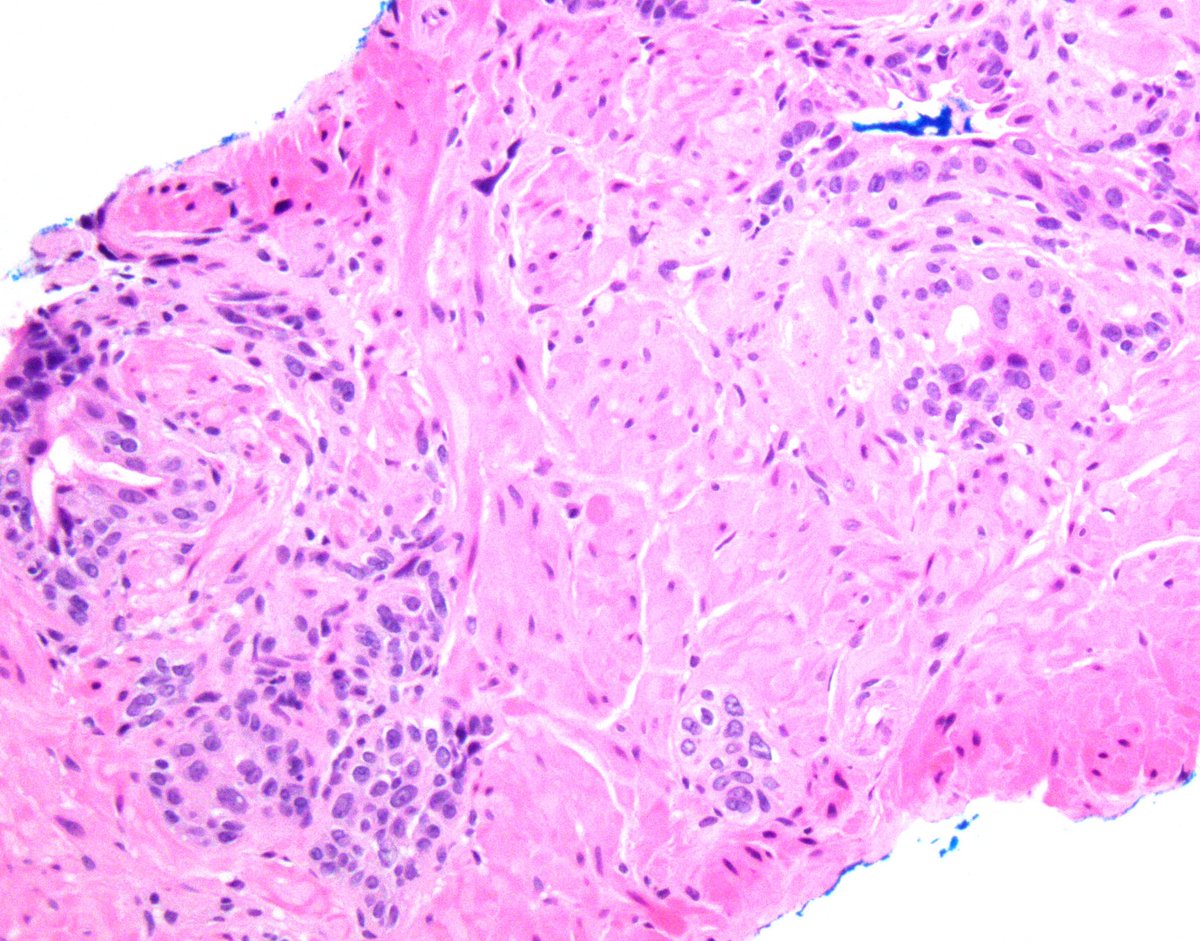

Great to catch up with @ESadimin during #KCRS2024. “It’s all about negative margins.” @CityofHope_GU @OSUCCC_James @OSU_Urology

Pathologist at City of Hope specializing in clinical informatics and urological pathology